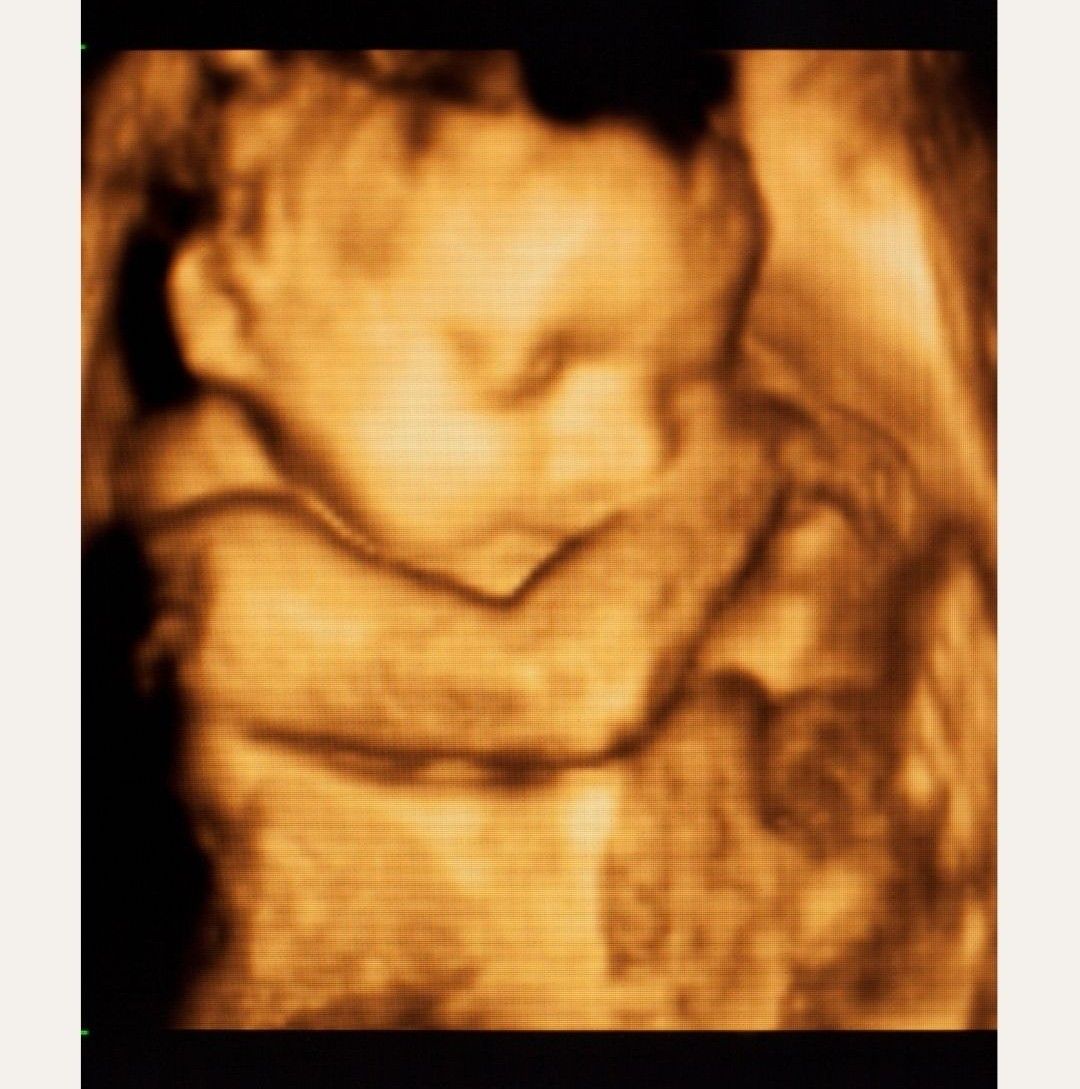

- Położnictwo i ginekologia